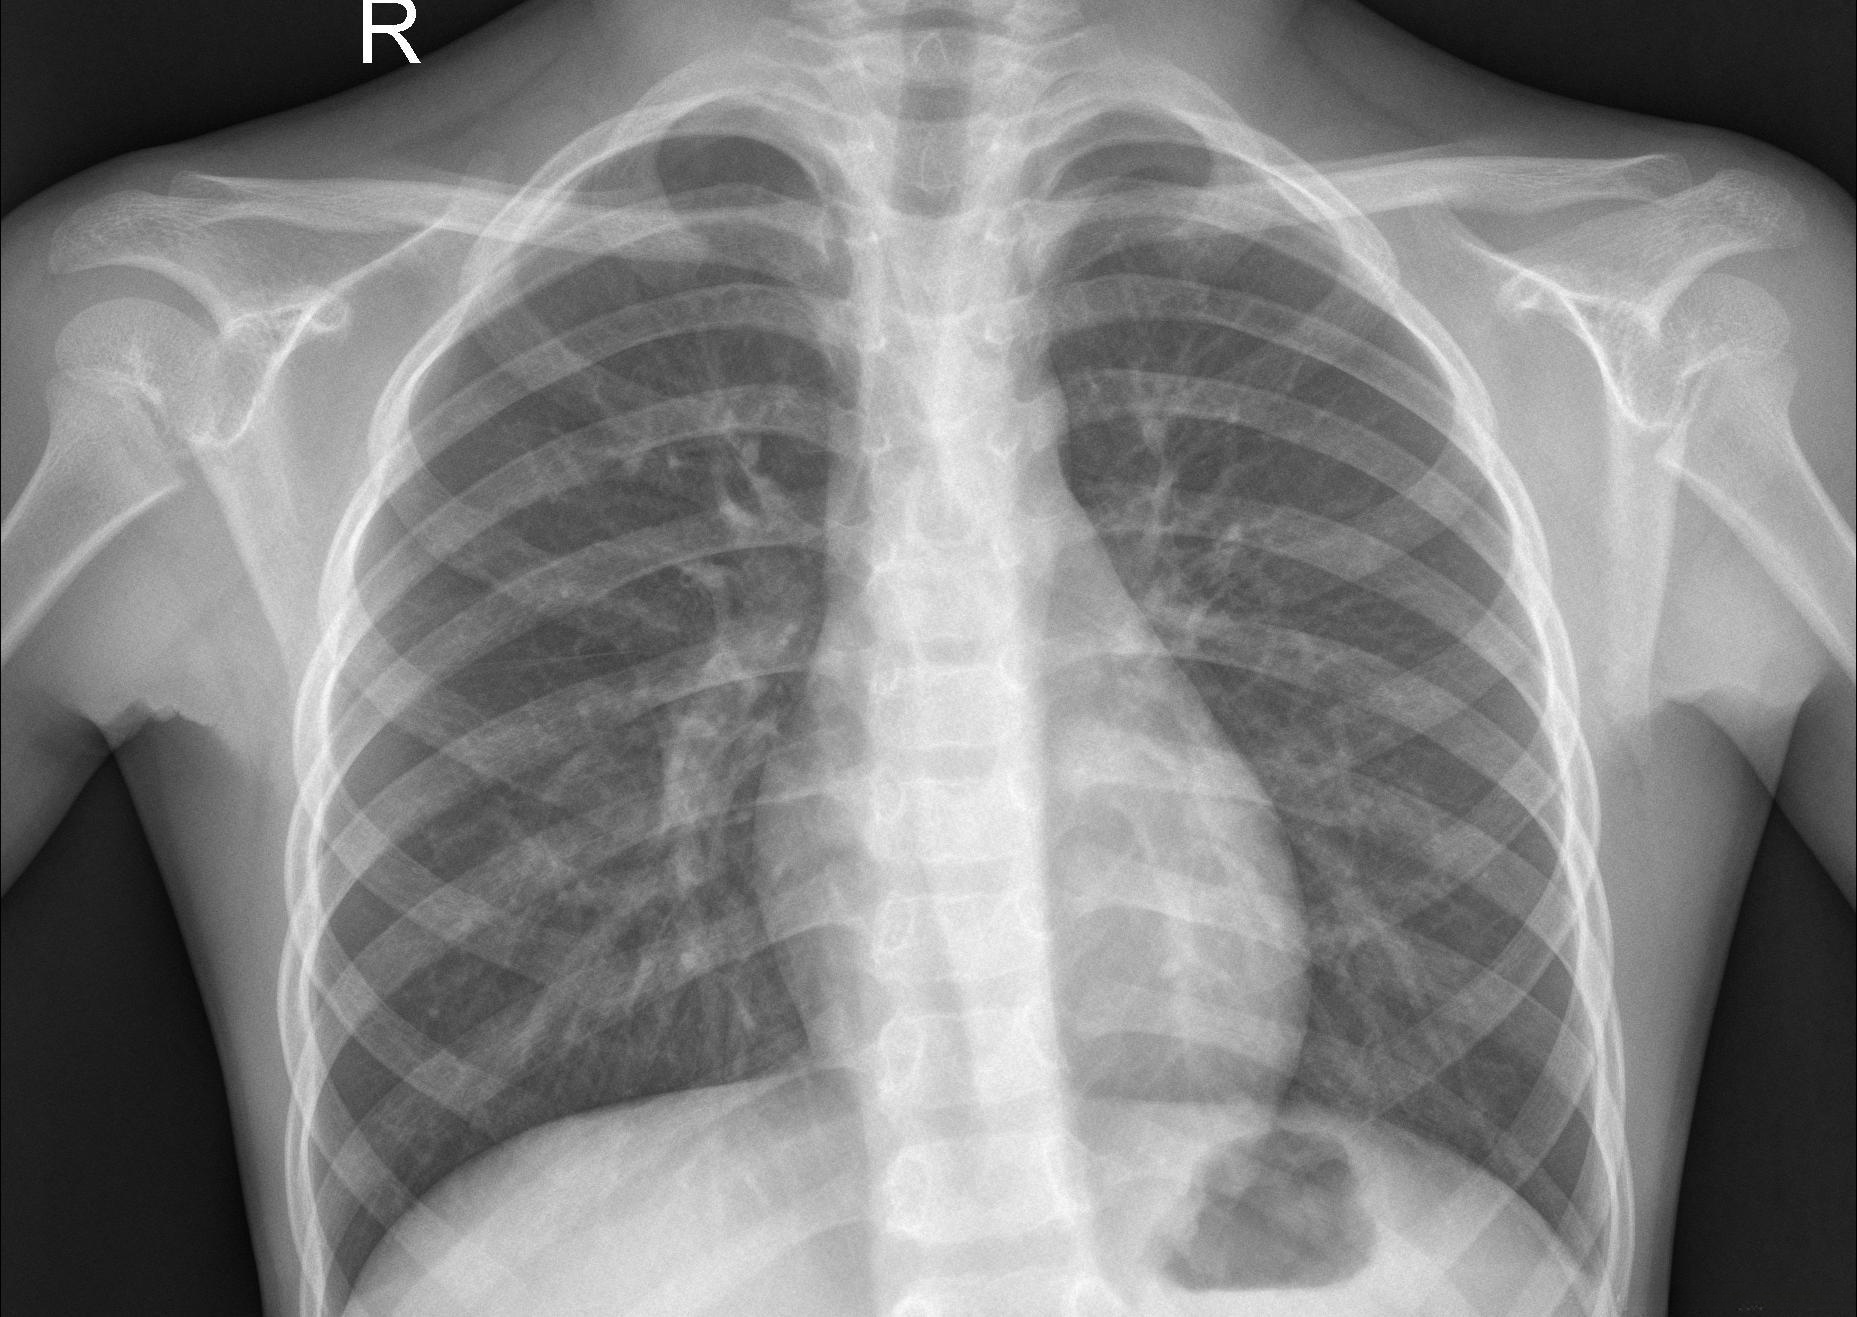

如下图为随机的两张正常的X射线图片